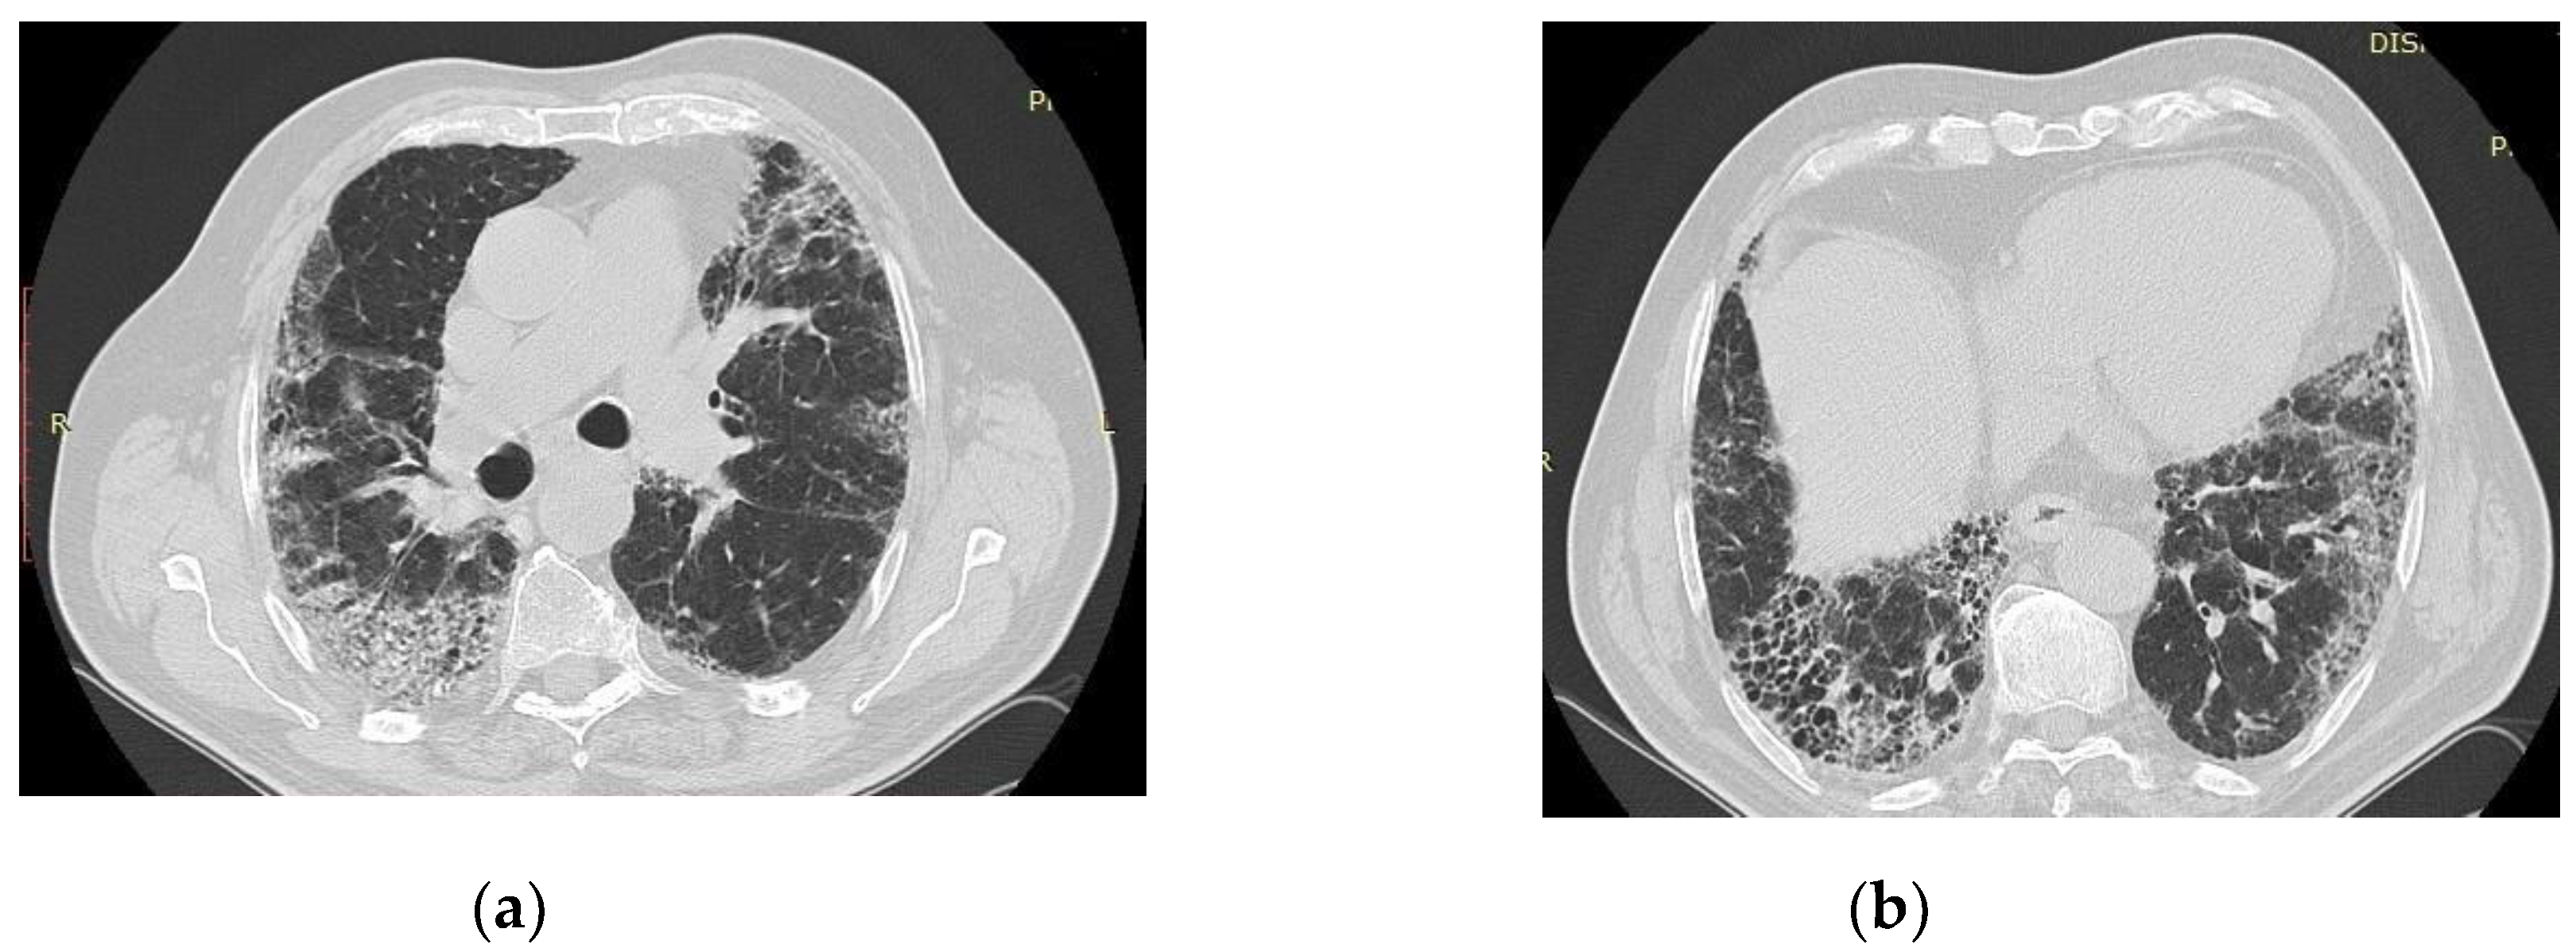

6. Radiologic aspects

- Wei, J.; Yang, H.; Lei, P.; Fan, B.; Qiu, Y.; Zeng, B.; Yu, P.; Lv, J.; Jian, Y.; Wan, C. Analysis of thin-section CT in patients with coronavirus disease (COVID-19) after hospital discharge. J. X-Ray Sci. Technol. 2020, 28, 383–389. [Google Scholar] [CrossRef]

- Francone, M.; Iafrate, F.; Masci, G.M.; Coco, S.; Cilia, F.; Manganaro, L.; Panebianco, V.; Andreoli, C.; Colaiacomo, M.C.; Zingaropoli, M.A.; et al. Chest CT score in COVID-19 patients: correlation with disease severity and short-term prognosis. Eur. Radiol. 2020, 30, 6808–6817. [Google Scholar] [CrossRef]

- Yin, X.; Xi, X.; Min, X.; et al. Long-term chest CT follow-up in COVID-19 Survivors: 102-361 days after onset. Ann Transl Med 2021, 9, 1231. [Google Scholar] [CrossRef]

- Vijayakumar, B.; Tonkin, J.; Devaraj, A.; Philip, K.E.J.; Orton, C.M.; Desai, S.R.; Shah, P.L. CT Lung Abnormalities after COVID-19 at 3 Months and 1 Year after Hospital Discharge. Radiology 2022, 303, 444–454. [Google Scholar] [CrossRef]

- Combet, M.; Pavot, A.; Savale, L.; Humbert, M.; Monnet, X. Rapid onset honeycombing fibrosis in spontaneously breathing patient with COVID-19. Eur. Respir. J. 2020, 56, 2001808. [Google Scholar] [CrossRef]

- Balestro, E.; Cocconcelli, E.; Giraudo, C.; Polverosi, R.; Biondini, D.; Lacedonia, D.; Bazzan, E.; Mazzai, L.; Rizzon, G.; Lococo, S.; et al. High-Resolution CT Change over Time in Patients with Idiopathic Pulmonary Fibrosis on Antifibrotic Treatment. J. Clin. Med. 2019, 8, 1469. [Google Scholar] [CrossRef] [PubMed]